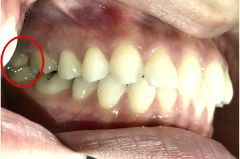

男性 Mさん 50代 (オールセラミック冠)

主訴

右上奥歯が、冷たいものにしみる。

治療内容

歯髄(神経および血管)まで到達する大きな虫歯でしたので、抜髄(歯髄を取り除く)をし、ファイバーコアをいれ、オールセラミック冠を被せました。

所感

現在、保険治療において、限定的ではありますが、大臼歯にも白い被せ物(プラスチック冠)ができるようになりました。しかし、実感としてプラスチック冠は、

- すり減りやすい。割れることがある。

- バイオフィルム(細菌およびそれから産生される副産物の塊)が付着しやすいので、歯周病および2次カリエス(被せ物と自分の歯の境目から再度虫歯になる)になるリスクが高い。

- 変色する。

という点を感じます。白い被せ物が保険の治療でできるという理由で、安易にプラスチック冠を選択し、割れたりすり減ったり、変色したらもう一度被せなおせばいいと考えるのであれば、一度立ち止まって考えてみてください。歯の量は、治療するたびに薄く少なくなり、歯根破折のリスクが高まります。もし大きな虫歯になってしまったら、最高レベルの根管治療をし、最良の被せ物であるオールセラミック冠を被せ、定期的にお口の中のクリーニングをし、同じ歯を2度と治療しないことが、歯を長持ちさせる最良の方法だと考えます。

オールセラミック冠(失活歯):¥104,500(税込)

Before

劣化したプラスチック冠

After